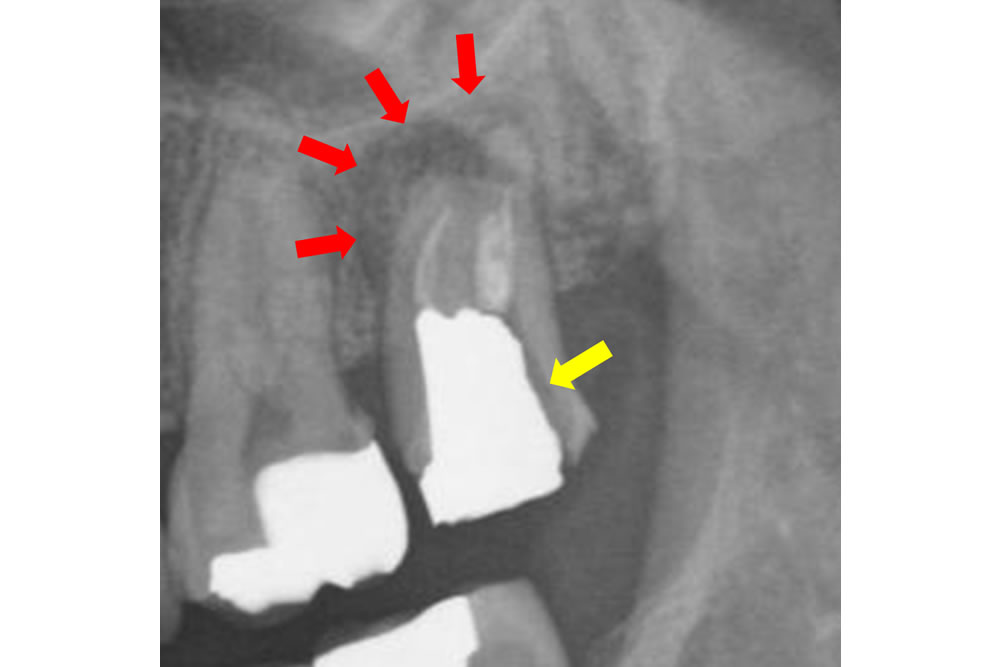

治療から約1年半後のレントゲン写真・CT画像

この写真だけですと、歯根の一部に黒い影が見られますが(赤矢印)、おおむね良好に見えます。

しかし、CT撮影してみると先ほどのレントゲンよりも黒い影(顎の骨が吸収している)の範囲が広かったことが確認できました。

ですが、幸い手前の歯までは広がっておらず、歯を支えている顎の骨も何とか維持できている(青矢印)ので、その点はかろうじて及第点かと思います(抜歯を回避して1年半経過したという意味で)。

とはいえ、今後この顎の骨が吸収している範囲が広がっていかないか?日常生活に支障が出るような症状が再び出てこないか?はやはり心配ですので、引き続き要観察だと考えております。